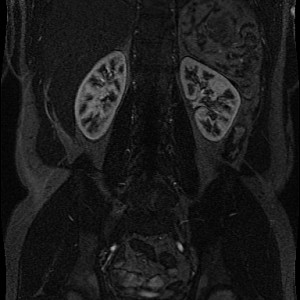

Example of MR Angiography with recording time before and after contrast agent infusion, respectively:

What do we see: Mainly kidneys, liver and and main supporting vessels aggregate contrast agent.